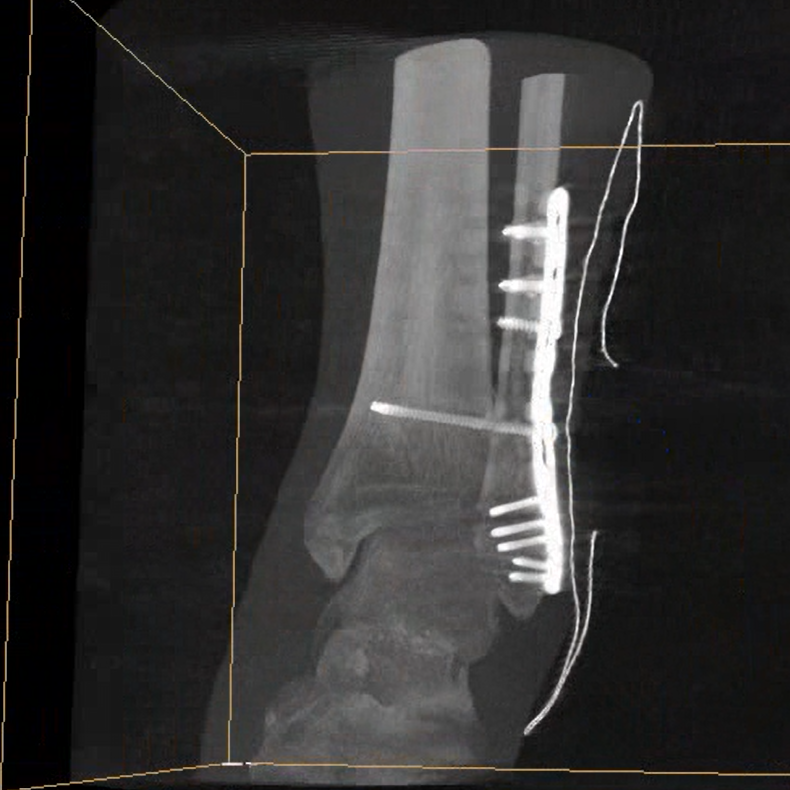

術(shù)中三維成像和橫斷面圖像提供多角度的手術(shù)診斷信息,輔助醫(yī)生進(jìn)行術(shù)中評估判斷,諸如骨折復(fù)位情況和內(nèi)植入螺釘?shù)某叽绾臀恢?,輔助手術(shù)更好地完成。